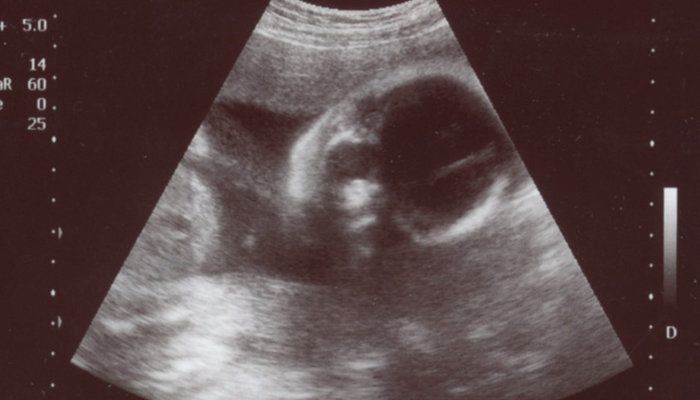

くろみつさんの妊娠26週目のエコー写真 画像におさまりきらないわが子の成長に感動

お顔を反対側に向けた頭部のエコー画像です。体は左側にあります。赤ちゃんの体重が1kgを超え、私のおなかも妊婦らしくなってきました。エコーでは赤ちゃんの体全部が入らなくなり、大きくなったことを実感しました。診察の際には、足をのばして、のびのびしている姿を見ることができておもしろかったです。私の体調は安定しており、法事のため新幹線で出かけたり、仕事も忙しかったり、妊娠前のようにバタバタと過ごしていました。